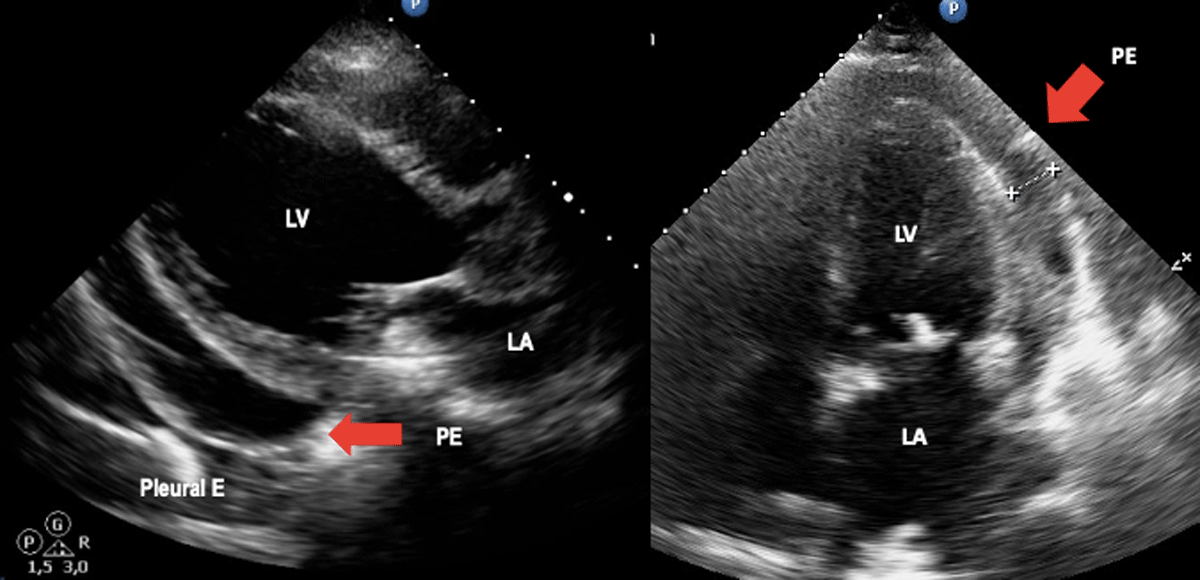

In patients with clinically suspected acute ChD, echocardiography should be performed to assess for functional abnormalities, evaluate the presence of pericardial effusion, and to assess for the presence of acute myocarditis (Figure 2). In endemic countries or in patients from these countries presenting in non-endemic environments, a febrile illness accompanied by abnormalities in myocardial wall motion and/or pericardial effusion should raise the possibility of acute ChD in the differential diagnosis.

Figure 2

Acute Chagas disease. Arrows indicate pericardial effusion in heart failure due to Chagas disease. Image: Mariana Corneli. Reproduced with permission of the photographer.

Global systolic function is rarely compromised, and wall motion abnormalities are usually segmental and focal [23]. In a series of 52 acute ChD myocarditis cases, the most common echocardiographic finding was pericardial effusion, which was detected in 42% (22 of 52) of the cases (mild to moderate in 17 and severe to massive in 5) [27]. Thus, among those with acute ChD who present with cardiomegaly on X-ray, echocardiography is more likely to detect pericardial effusion rather than chamber dilatation. In the case of a documented pericardial effusion, careful assessment for hemodynamic compromise should be performed. In Table 2 the stages of cardiac involvement in ChD are represented.